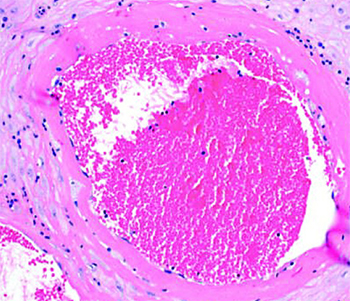

Рисунок 4. Тромбоз межворсинчатого пространства (5-кратное увеличение). Тромбоз межворсинчатого пространства (см. рис. 4). В сосудах формируются слоистые тромбы, оттесняя на периферию ворсины, которые перестают участвовать в газообмене.

Иван Сахаров обратил внимание, что изменения настолько яркие, что видны на макроскопическом уровне. Если в норме плацентарная ткань рыхлая, насыщенного красного цвета и напоминает пропитанную кровью губку, то при тромбозе становится желтовато-серой, очень плотной и сухой. В ней имеются заполненные кровью участки — это кровоизлияния и формирующиеся тромбы.